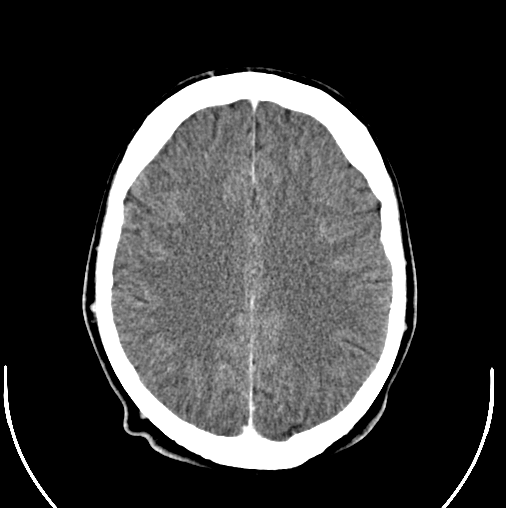

In the initial Health, Aging and Body Composition study group of 2,552 dementia-free older adults (mean age 76.1 years), 15.4% or 392 patients were anemic at baseline. Anemia was defined as a hemoglobin concentration of <13 g/dL for men and <12 g/dL for women; dementia was defined as a score of more than 1.5 SD from mean on the Modified Mini-Mental State (3MS) scale.

Over the 11 years of follow-up, 455 (17.8%) participants developed dementia. Researchers found that those with baseline anemia had 23% risk of dementia vs. 17% for those without anemia. Furthermore, neither sex nor race impacted the risk of developing dementia.

“There are several explanations for why anemia may be linked to dementia. For example, anemia may be a marker for poor health in general, or low oxygen levels resulting from anemia may play a role in the connection. Reductions in oxygen to the brain have been shown to reduce memory and thinking abilities and may contribute to damage to neurons," said study author Kristine Yaffe, MD, of the University of California San Francisco and a member of the American Academy of Neurology.